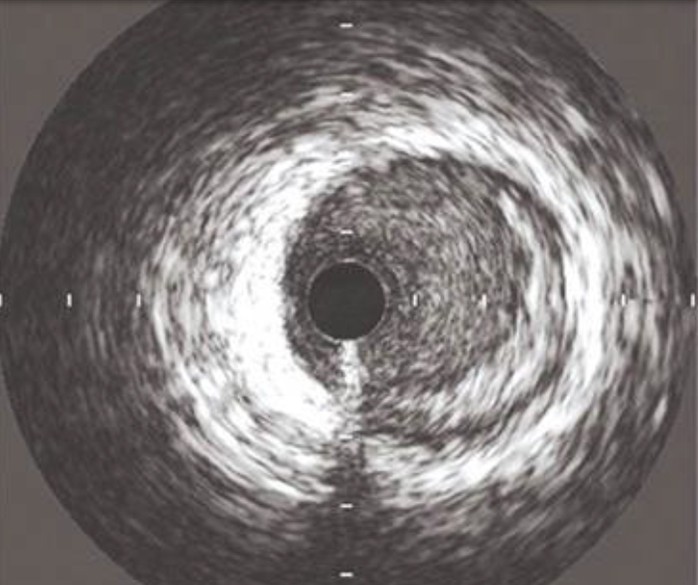

Catéter para toma de imágenes coronarias Opticross de 60 MHz vs. OCT

OPTICROSS 60 MHz

Catéter de imágenes OPTICROSS HD 60 MHz

OCT